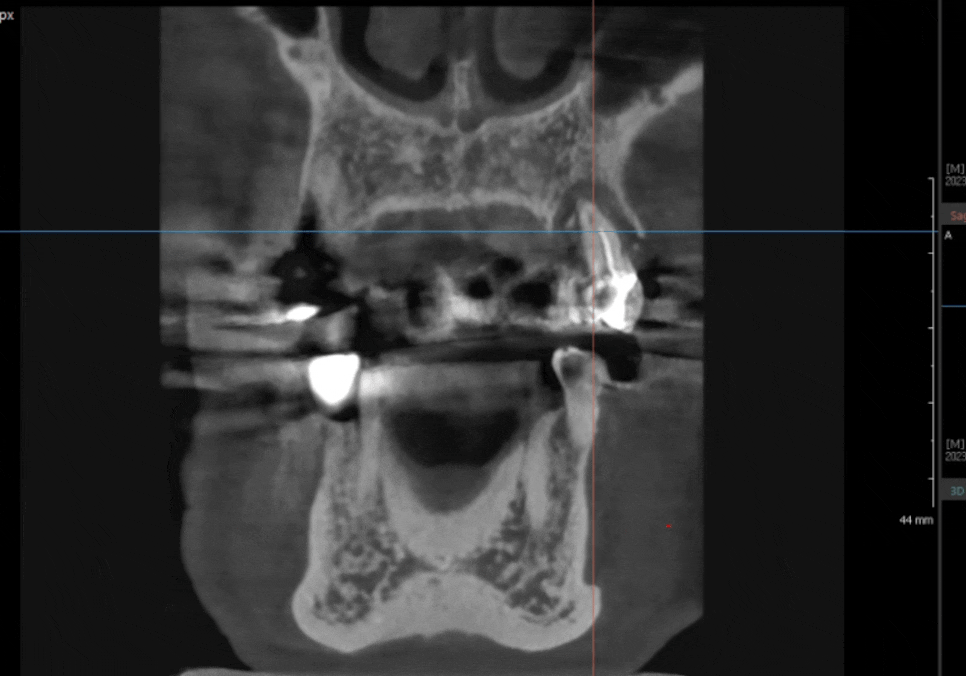

231124

수술 부위의 염증을

최대한 깔끔하게 긁어내고,

그 자리에 바로 뼈이식과 임플란트를 심어드려

외과적 수술을 단 한 번으로 끝내 드렸습니다.